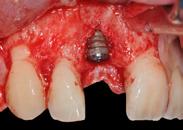

C’est une cheville en titane ou en céramique qui se propose de remplacer la racine de la dent. À ce titre, l’implant est placé dans l’os et relié dans un second temps à une couronne.

Quand on parle d’implantologie, on distingue une phase chirurgicale : mise en place de l’implant dans l’os (= remplacement de la racine perdue) et une phase prothétique : mise en place de la couronne sur l’implant.